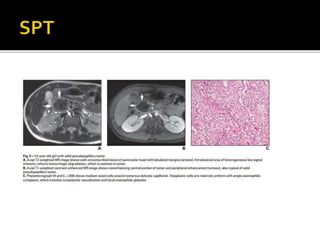

 Descrito en 1959.

 1-2% de todos los tu de

páncreas.

 F:M 9:1 , adultos jóvenes:25 a

 Africanos y asiáticos.

 Bajo potencial maligno con

excelente pronóstico luego de la

resección.

 Mtt: 7-9%: hígado, omento,

peritoneo.

 Clínica: dolor y masa abdominal.

 Características

morfológicas:

 Grande x: 9 cm.

 Crecimiento lento.

 Masa bien encapsulada.

 Cola > cabeza.

 Desplaza más que invade,

raro obstrucción biliar

 Hipodenso enTC, baja

señal enT1 yT2.

 Hemorragia interna y

degeneración quística

 Hemorragia hiper-aguda:

hiperintensa enT1 con intensidad

de señal variable enT2.

 Hemorragia crónica: hipointensa

en ambas secuencias.

 Nivel fluido-fluido/ fluido –debris:

10-18% por efecto del

hematocrito.

 Calcificaciones periféricas 30%.

 Realce heterogéneo periférico

durante la fase arterial y realce no

uniforme periférico pero

agresivo. (realce menor que el

páncreas)